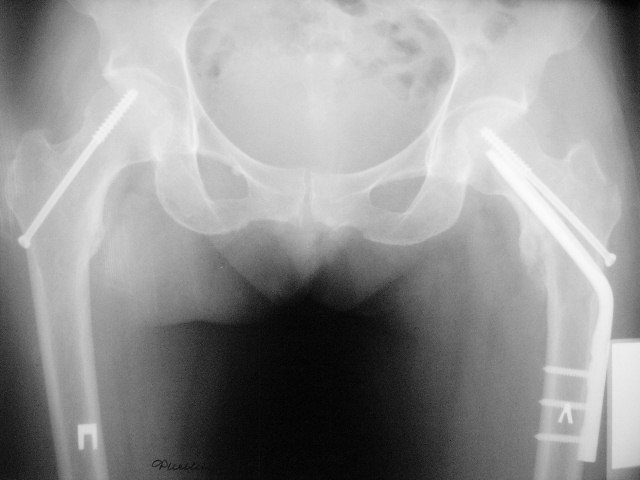

На Московской конференции в ноябре была продемонстрирована удивительная методика профилактического армирования шейки бедра у пациенток с остеопорозом и переломом контрлатеральной шейки в анамнезе.Странно, но дискуссии это сообщение не вызвало.Кто что думает об этом?

Спасибо, Антон. Я автор того сообщения по профилактическому армированию шейки бедренной кости, которое прозвучало на конференции, посвященной 50-летию создания АО. Мне тоже хотелось услышать вопросы по теме. Мы травматологи-ортопеды в первую очередь хирурги, а не терапевты. Почему в вопросе профилактики и лечения остеопороза мы ограничиваемся только консервативными методами лечения? Как можно практически научить больного не получать травмы, когда немало случаев возникновения переломов даже в постели. Первоначально идея армирования ШБК многих, при ком я озвучивал ее, шокировала, затем возникала дискуссия и большинство поддерживали эту идею. Мне бы очень хотелось развернуть дискуссию на странице этого сайта.

Уважаемый Антон! У меня было всего три клинических наблюдения, снимки были продемонстрированы на московской конференции. Количества этих снимков хватило для подачи заявки, а затем и получения патента на изобретение. В свое время РОСПАТЕНТ потребовал подтверждения методики клиническими наблюдениями. У одной из больных действительно произошла повторная травма, и произошел подвертельный перелом на стороне армированной шейки бедренной кости (см. снимки). Это подтвердило основную идею изобретения - была сохранена и головка, и армированная шейка бедренной кости. Но тут не обошлось безпроблем. Анестезиологи отказались давать наркоз, а провести остеосинтез под м/а пластиной и винтом DHS не согласилась больная. Дальнейшее лечение скелетным вытяжением. На контр. Рентгенограмме через 2 месяца признаки формирования костной мозоли. Повторных обращений двух других пациентов не было. Для более детальных исследований и выводов необходимо значительно большее количество клинических наблюдений. Такие исследования могли быть проведены в условиях клиник медуниверситета. Напомню, я работаю в травмотделении провинциальной городской больницы. Насчет экспертов страховых компаний, так пусть они выскажут свое мнение. Армирование кости - это плановые операции по желанию больного, какие здесь могут быть противоречия? На армирование все больные, к моему удивлению, согласились довольно легко и сразу, поэтому остеосинтез и армирование были проведены в течение одной операции. С уважением А.М.

Не ради критики, но меня заинтересовал предложенный доктором Матвеевым хирургический приговор - профилактика несовершенного перелома шейки у пожилых армированием.

В нашей практике сталкиваемся с хирургическими методиками профилактики перелома костей, и поэтому заинтересовался предложенным методом.

Мне кажется, во-первых, трудно определить абсолютные показания. Метод не может быть применен у всех, если даже у больных имеются подозрение на остеопороз с другой стороны.

Кстати, очень сомнительна остеопорозность на правом оперированном бедре, отсутствует данные денситометрии с индексом остеопороза.